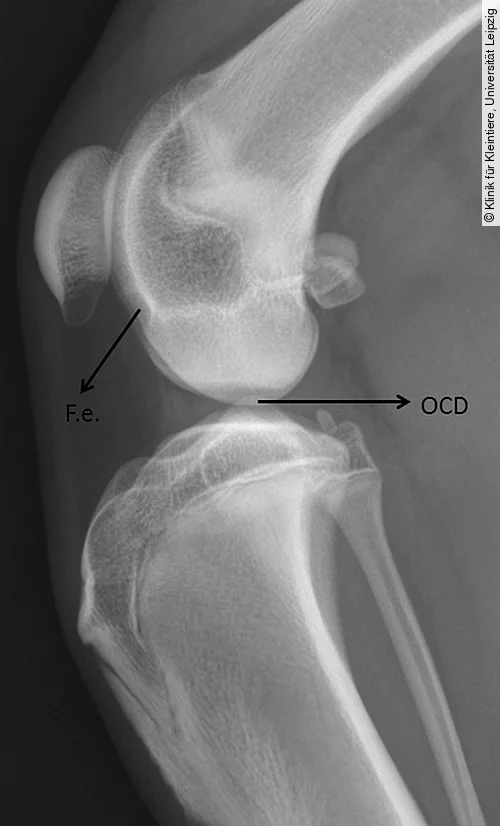

Für die Darstellung der OCD am lateralen und medialen Condylus femoris wird eine mediolaterale und eine kraniokaudale oder kaudokraniale Röntgenaufnahme benötigt. Obwohl die mediolaterale Aufnahme häufig schon pathognomonische Anzeichen der OCD zeigt, ist eine kraniokaudale oder kaudokraniale Projektion erforderlich, um festzustellen, welcher Kondylus betroffen ist [4].

Die Röntgenbilder können Veränderungen wie eine Abflachung der Gelenkoberfläche an einem der beiden Femurkondylen (meist Medialfläche lateraler Kondylus), einen konkaven Defekt am subchondralen Knochen (mit oder ohne angrenzende Sklerose) oder selten mineralisierte Knorpelschuppen zeigen (Abb. [ 6 ], Abb. [ 7 ]).

Differenzialdiagnostisch kann es zu einer Verwechslung der normalen Fossa extensoria (Ursprung M. extensor digitorum longus) mit einer OCD-Läsion kommen. Die Fossa resultiert aber im Gegensatz zur OCD-Läsion nicht in einem Defekt der Gelenkfläche (kraniokaudale Projektion) und ist auf der mediolateralen Aufnahme deutlich weiter kranial und proximal lokalisiert (Abb. [ 6 ]) [4], [22].